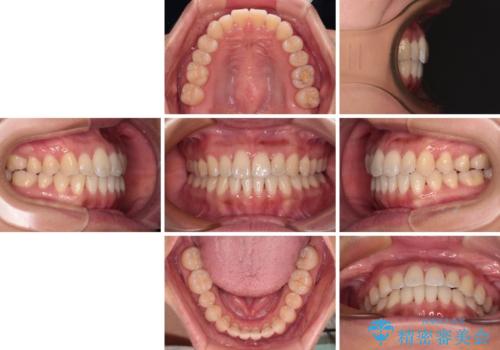

- 前歯のデコボコで前方に出ていることを気にして来院された患者様です。

上顎前歯が捻れて前方に飛び出しており、下顎前歯もそれに沿うようにデコボコとなっていました。

IPR(歯と歯の間を削る処置)によりスペースを獲得して上下顎前歯のデコボコを改善し、飛び出している前歯が引っ込むように設定し、インビザラインにて矯正治療を行うこととしました。

装着時間を守ってくださったので、予定通りの期間で終えることができました。インビザライン特有の、奥歯の咬み合わせの問題もなく、しっかりと歯列を改善することができました。